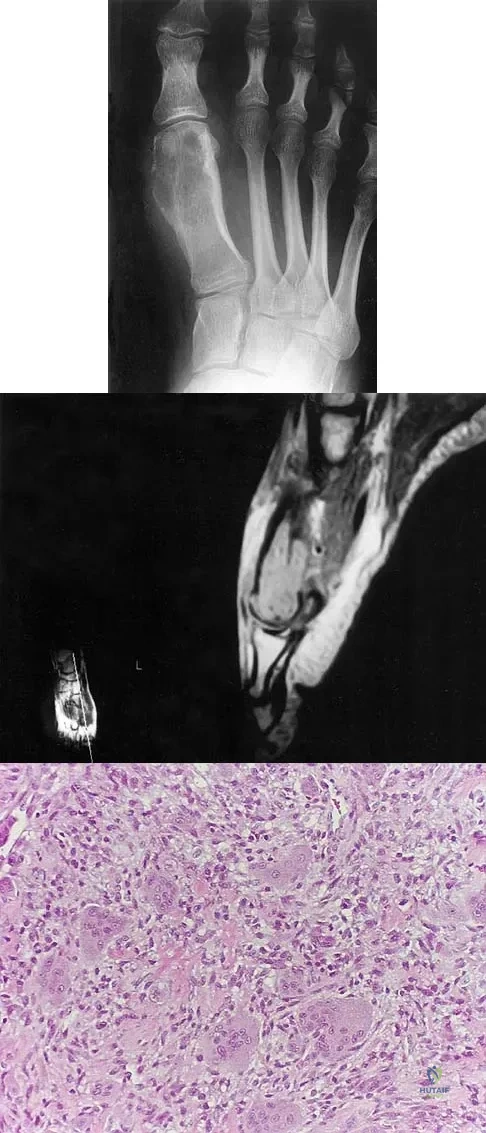

Question 60

A 20-year-old patient has foot pain. A radiograph and T1-weighted MRI scan are shown in Figures 8a and 8b. A biopsy specimen is shown in Figure 8c. Treatment should consist of

Explanation